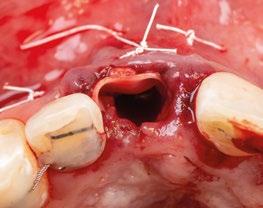

7.- Interponemos membrana reabsorbible entre tejido conectivo y alveolo. (Figuras 20 y 21)